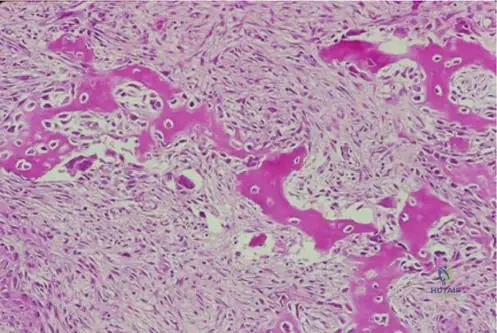

A bone biopsy is performed on a 9-year-old patient with a lytic lesion in the tibia. Histological examination reveals benign, proliferating fibroblastic cells and islands of woven bone arranged in an erratic pattern.

View Answer & Explanation

Correct Answer: A

Rationale: The text states, "The bony trabeculae area arranged in an erratic pattern sometimes referred to as “an alphabet soup”." This is a pathognomonic histological description for fibrous dysplasia. Main Distractor Rationale: Option B is incorrect. A mosaic pattern of bone is characteristic of Paget's disease, not fibrous dysplasia.

Question 55

A pathologist is reviewing a biopsy specimen from a patient with suspected fibrous dysplasia.

A 12-year-old female presents with a several-month history of right thigh pain and a limp. Radiographs reveal a well-circumscribed lytic lesion in the proximal femur with a sclerotic rim and a hazy, increased density described as "ground glass" appearance. A biopsy is performed.

Correct Answer: C

Rationale: Histologically, fibrous dysplasia is characterized by benign, proliferating fibroblastic cells and islands of woven bone arranged in an erratic pattern, often described as "alphabet soup." This is a classic description for fibrous dysplasia. Option D describes a giant cell tumor, and Option E describes osteosarcoma, neither of which matches the benign fibro-osseous nature of fibrous dysplasia.